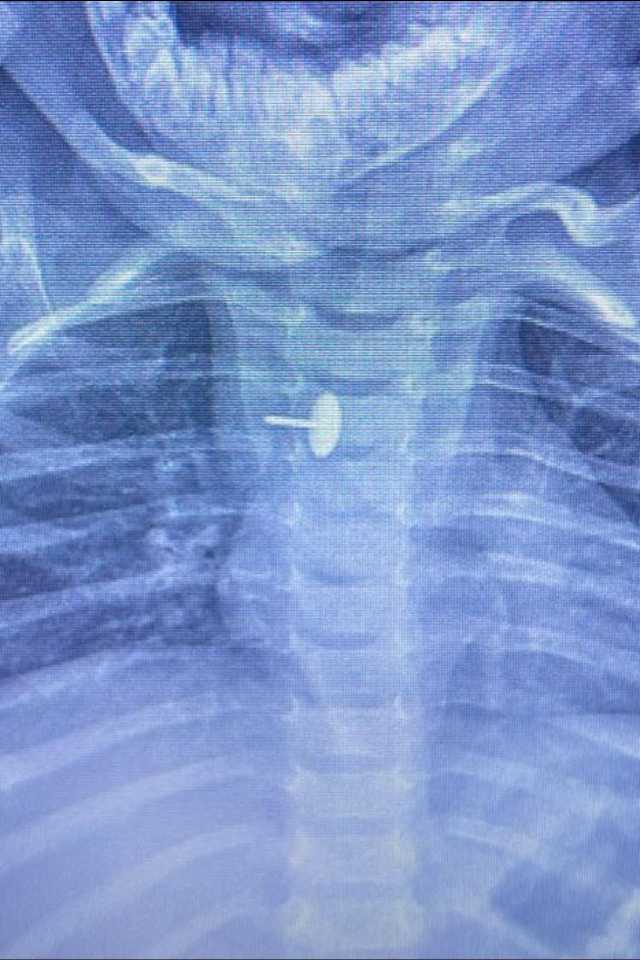

نجح فريق قسم جراحة الأطفال، بمستشفى الأطفال التخصصي ببنها، بمحافظة القليوبية، بقيادة الدكتور محمد متولي رئيس قسم جراحة الأطفال، في إجراء عملية دقيقة لاستخراج دبوس ضغط من مريء طفلة عمرها سنة و7 أشهر، كانت قد ابتلعته منذ 6 أشهر.

كشفت مستشفى الأطفال التخصصي ببنها، في بيان لها، أن الجسم الغريب استقر داخل جدار المريء، مما تسبب في عدم قدرة الطفلة على البلع طوال هذه الفترة، وجعل حياتها في خطر دائم.

أوضحت المستشفى أن العملية تمت باستخدام منظار الجهاز الهضمي، وجهاز الأشعة "سي- آرم"، ومنظار القصبة الهوائية، وسط أعلى درجات التركيز والدقة، ليكتب الأطباء نهاية سعيدة لقصة مليئة بالتوتر والخطر